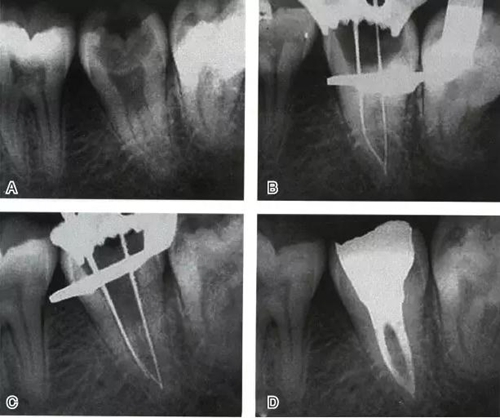

根管充填是C形根管治療成功與否的最重要因素。充填C形根管系統(tǒng)時,近舌及遠中根管可以進行常規(guī)充填。關(guān)于狹區(qū)的充填,更適合以熱牙膠垂直加壓充填,這種方法可使牙膠到達根管系統(tǒng)的每一死角(圖4~7)。

圖5 Ⅰ型C形根管治療典型病例二,A:初始片,B:初尖銼片,C:主尖銼片,D:充填片

圖6 Ⅱ型C形根管治療典型病例,A:初尖銼片,B:主尖銼片,C:根充片,D:術(shù)后片